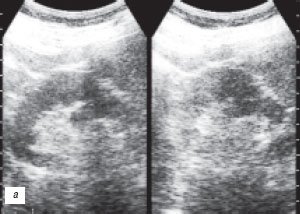

Наиболее частой причиной псевдоопухоли была "гипертрофия" столбов Бертена или "перемычки" паренхимы почек - у 153 (86,4%) пациентов (рис. 3 г-е). "Перемычки" паренхимы были отмечены не только при различных удвоениях чашечно-лоханочных систем почек, но и при различных их сращениях и незавершенных поворотах почек.

г) Эхограмма.

е) КТ с контрастным усилением.